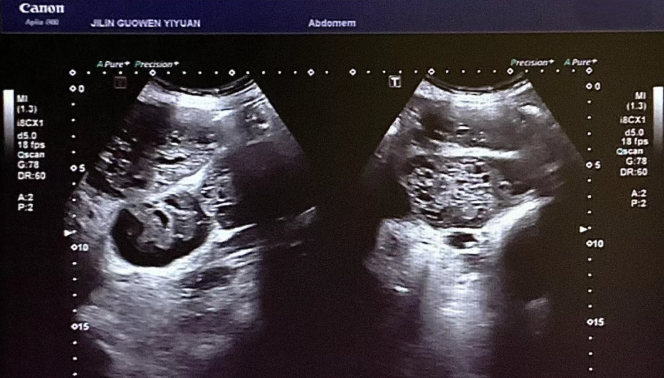

患者錢女士(化名),65 歲,因有高血壓病史而定期進(jìn)行體檢。在超聲檢查時,醫(yī)生發(fā)現(xiàn)其腎臟存在占位性病變。超聲科團(tuán)隊(duì)借助高分辨率超聲成像技術(shù),清晰地觀察到腎臟內(nèi)的異?;芈晠^(qū),再結(jié)合血流信號分析,高度懷疑該病變可能為惡性腫瘤。為進(jìn)一步明確診斷,團(tuán)隊(duì)在超聲引導(dǎo)下進(jìn)行精準(zhǔn)穿刺,獲取病理組織。最終,病理報告確診該病變?yōu)?“小圓細(xì)胞惡性腫瘤”。

小圓細(xì)胞惡性腫瘤是一類較為少見的惡性疾病,常見于兒童及青少年,而發(fā)生在老年患者腎臟的情況則更為罕見。此類腫瘤具有很強(qiáng)的侵襲性,早期診斷對于治療方案的制定以及患者的預(yù)后都至關(guān)重要。錢女士雖然沒有出現(xiàn)典型癥狀,腹部查體也未觸及包塊,但得益于超聲科的細(xì)致檢查,病灶被及時發(fā)現(xiàn),這為后續(xù)的治療贏得了寶貴時間。